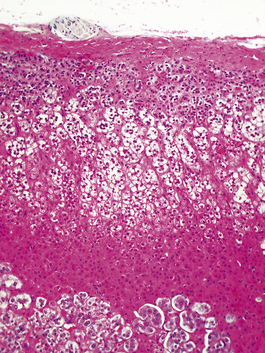

Hashimoto’s thyroiditis

Hashimoto’s thyroiditis may initially cause thyroid enlargement, but later there may be atrophy and fibrosis. The gland appears firm, fleshy and pale (Fig. 17.25). Histologically, the gland is densely infiltrated by lymphocytes and plasma cells, with lymphoid follicle formation. Colloid content is reduced, and the thyroid epithelial cells show a characteristic change in which they enlarge and develop eosinophilic granular cytoplasm due to proliferation of mitochondria; they are then termed Askanazy cells, Hürthle cells or oncocytes (Fig. 17.26). In advanced cases there may be fibrosis. Paradoxically, in the early stages of Hashimoto’s thyroiditis, the damage to the thyroid follicles may lead to release of thyroglobulin into the circulation, causing a transient phase of thyrotoxicosis.

Fig. 17.26 Histological features of Hashimoto’s thyroiditis. There is destruction of follicles by a dense lymphocytic infiltrate with germinal centre formation. Some of the surviving epithelial cells show Hürthle cell change (arrowed).